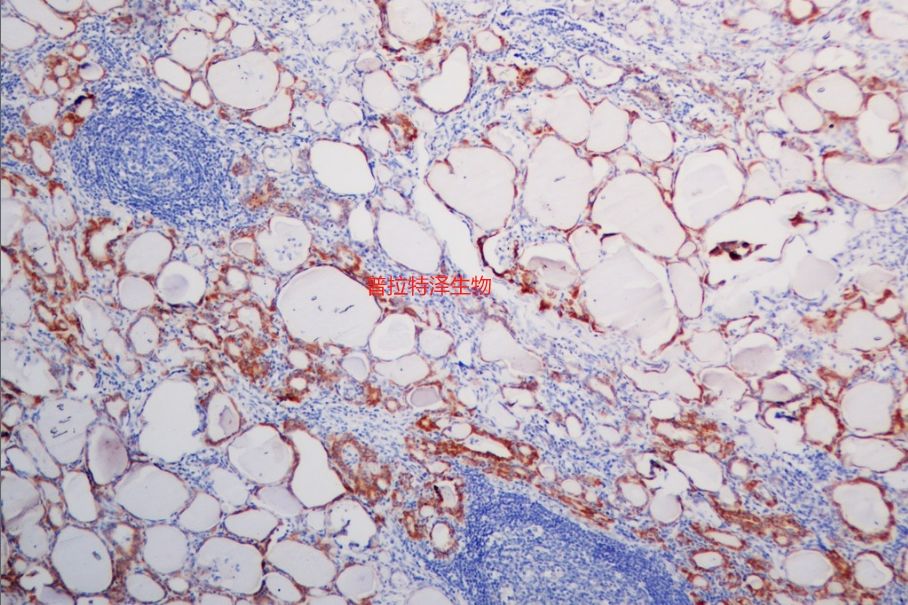

圖一熒光原位雜交

圖二原位雜交